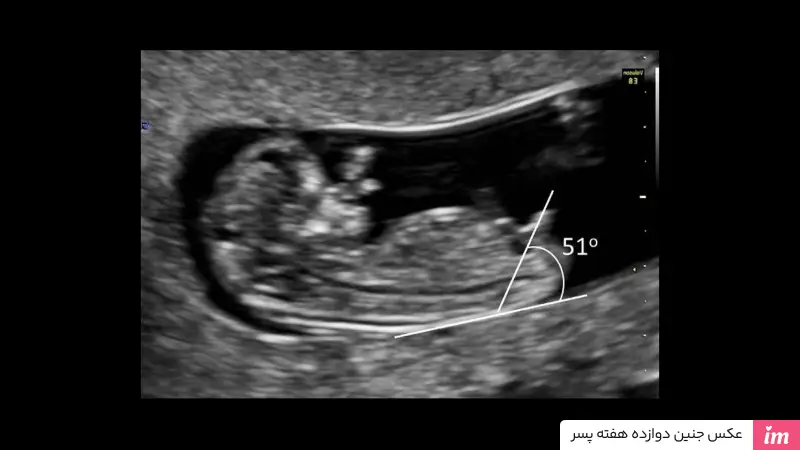

- روش تیر و کمانی

روش تیر و کمانی یکی از روشهای متداول و جالب در تعیین جنسیت و تفاوت جنین دختر و پسر در سونوگرافی هفته 12 میباشد. در این روش زاویه برآمدگی آلت تناسلی نسبت به ستون فقرات بررسی میشود. اگر زاویه برآمدگی بیشتر از ۳۰ درجه باشد، جنین پسر، و اگر زاویه کمتر از ۱۰ درجه باشد، جنین دختر است. اگر زاویه برآمدگی آلت تناسلی نسبت به ستون فقرات بین ۱۰ تا ۳۰ درجه باشد، شناسایی جنسیت قطعی نیست و باید تا سونوگرافی بعدی منتظر بمانید.

با توجه به توضیحات بالا میتوان گفت در سه ماهه ابتدایی بارداری مشاهده بیضههای جنین غیرممکن است. با این وجود، برخی اعتقاد دارند که در سونوگرافی هفته دوازدهم به کمک روش تیر و کمان میتوان جنین پسر را تشخیص داد.

کشف جنسیت جنین، همانند باز کردن هدیهای است که سالها منتظرش بودهاید. با انجام سونوگرافی، میتوانید اولین نگاه اجمالی به دنیای شگفتانگیز فرزندتان بیندازید و برای آینده برنامهریزی کنید. همه ما برای پیش بینی و فهمیدن جنینی که چشم به راهش هستیم هیجان داریم و به روشهای مختلف از بررسی علائم بارداری از روی چهره تا سونوگرافیها پناه میبریم. اگرچه در میان این روشها سونوگرافی بهترین و مطمئنترین روش در تعیین جنسیت او است، اما برای رسیدن نوبت آن باید کمی صبر کنید. سونوگرافی هفته 12 بارداری اهداف متفاوتی مانند تشخیص بیماریهای کروموزومی دارد که تعیین جنسیت جزء آنها نیست.، اما برخی از پزشکان و تکنیسینها با روشهایی از جمله روش تیر و کمانی تلاش میکنند تفاوت جنین دختر و پسر در سونوگرافی هفته 12 را تشخیص دهند.